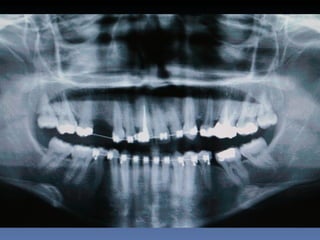

Plano de tratamento: Reabilitação bilateral maxilar

posterior-”Sinus-lift” ; 2 blocos ”onlay” na pré-maxila,

proveniente de Bloco de Fémur Homógeno Fresco-

congelado.

Mensuração pré-reabilitação :

1.1 ------ 3,0 mm

2.1 ------ 3,0 mm

Mensuração pós-reabilitação :

1.1 ------ 6,2 mm

2.1 ------ 6,3 mm